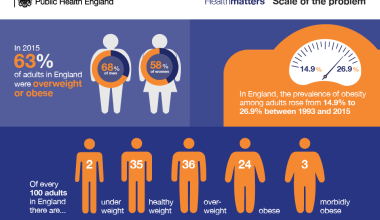

Mesothelioma Statistics in the UK

- The UK has one of the highest mesothelioma rates in the world.

- Over 2,500 new cases are diagnosed annually.

- Men are more commonly affected due to their prevalence in high-risk industries.